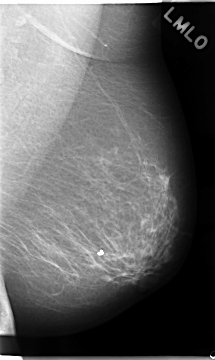

C_0051_1.LEFT_MLO

LEFT_MLO LINES 4680 PIXELS_PER_LINE 2792 BITS_PER_PIXEL 12 RESOLUTION 50 NON_OVERLAY